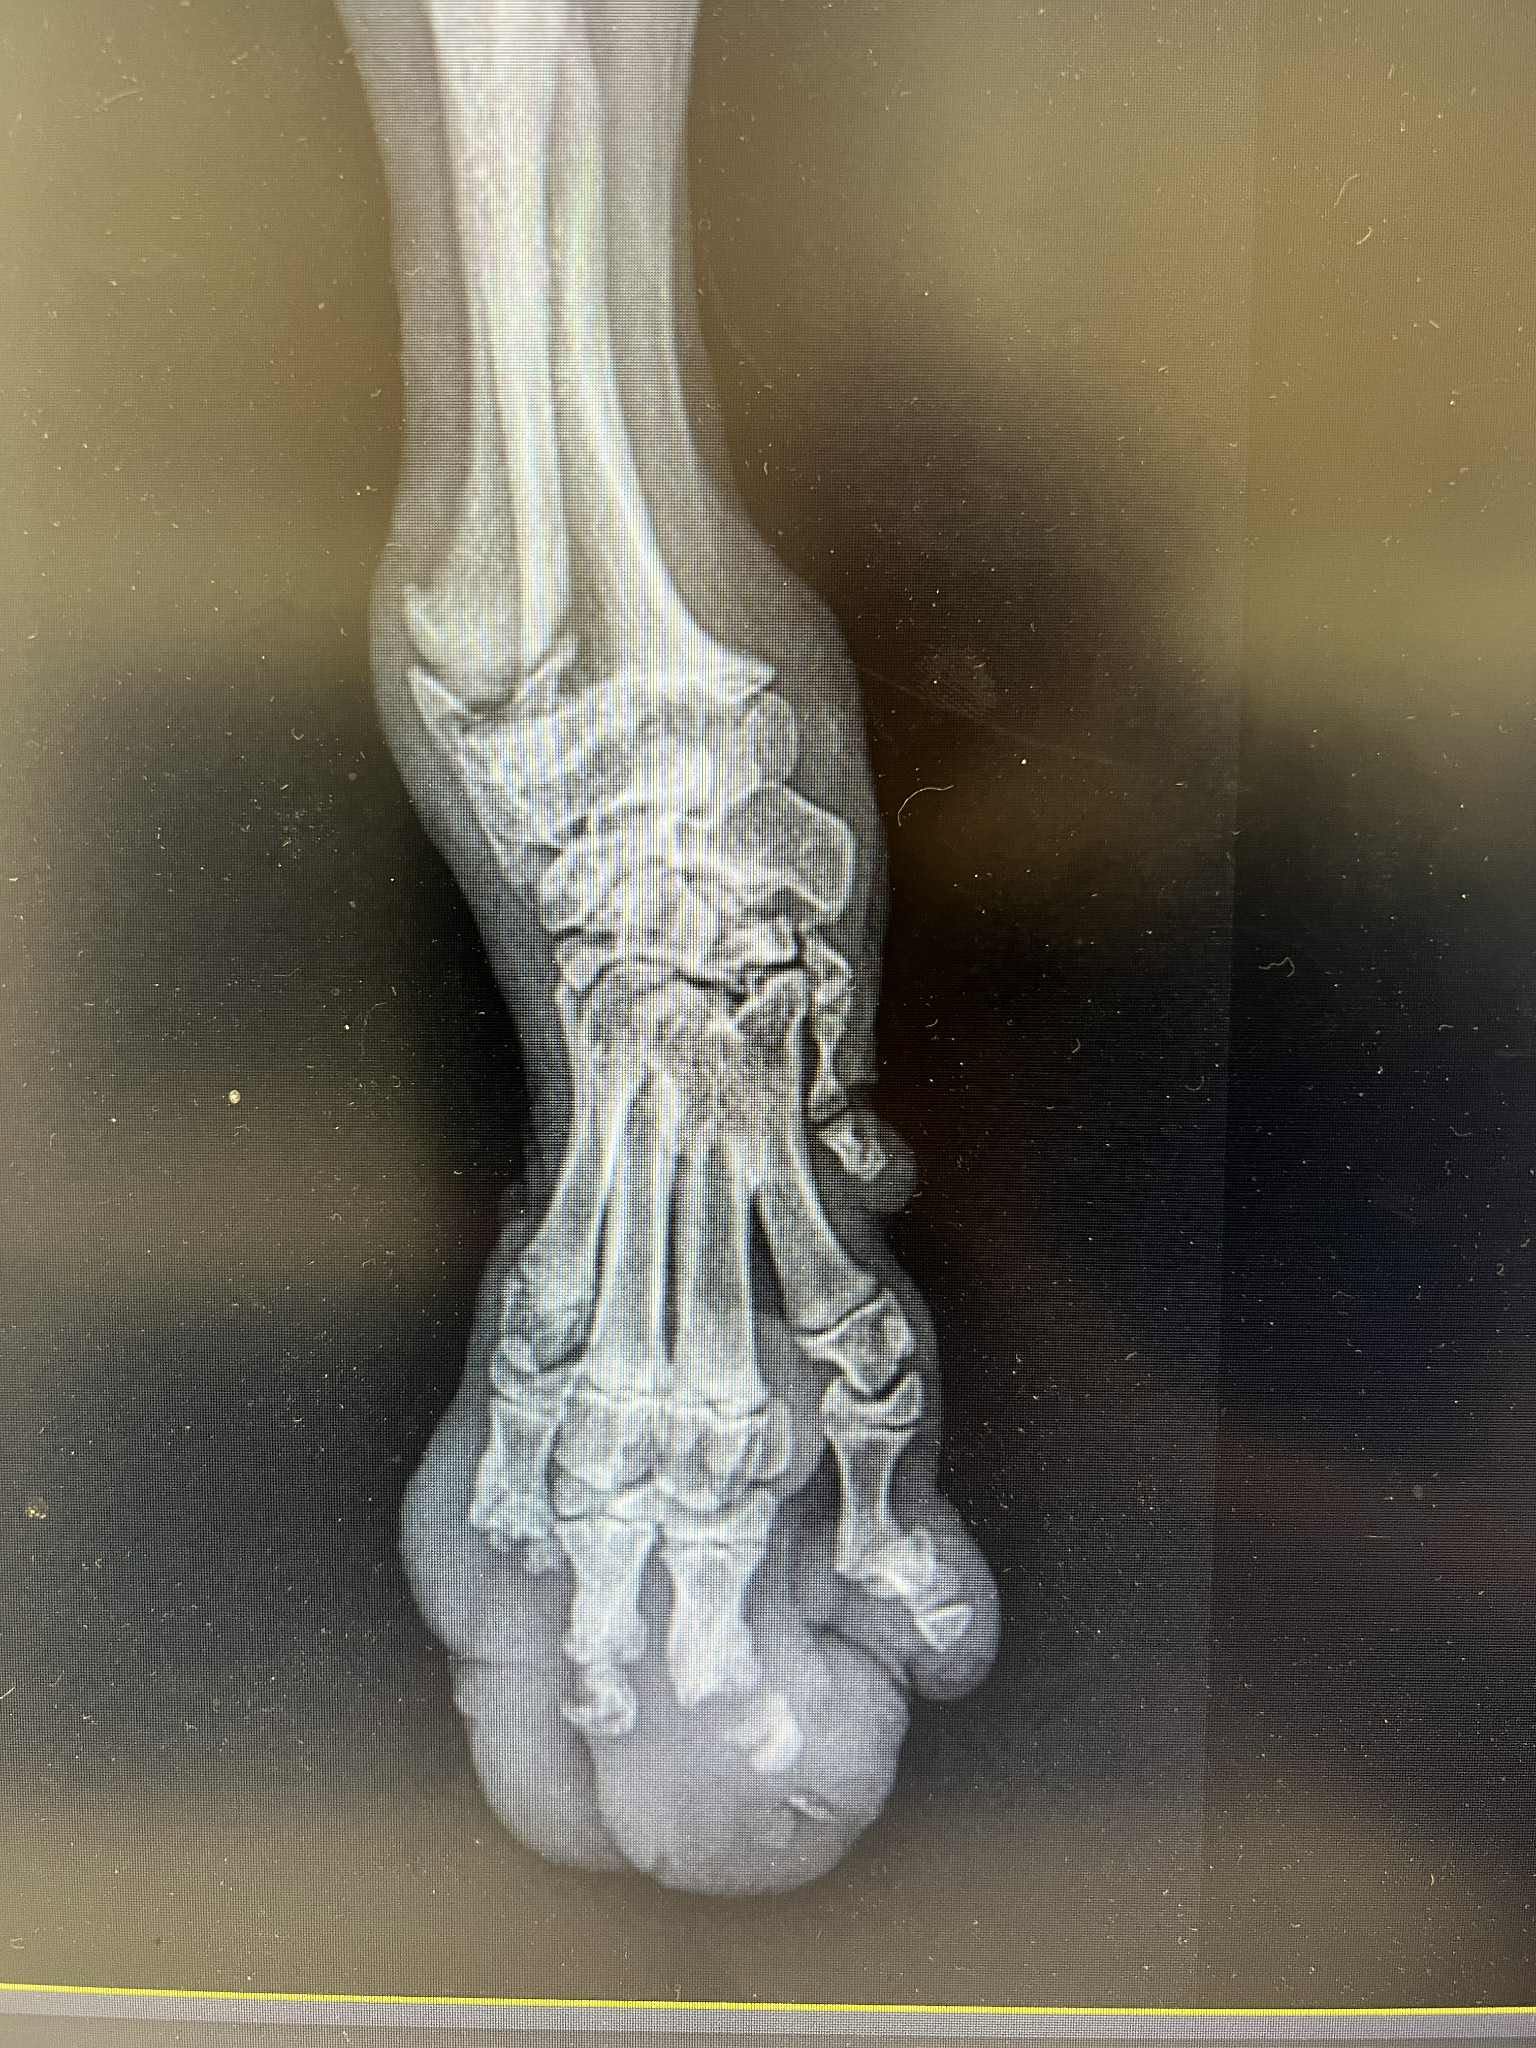

Laukas jau ne pirmą mėnesį leidžia prieglaudoje, o viskas dėl vaikystėje patirtos kojytės traumos. Labai gaila, bet kojos išsaugoti mums nepavyko, bet Laukas dėl to ir neliūdi, nes skuodžia kaip tornadas ant visų 3 savo letenų

O dabar apie sveikatą: Laukui amputuota letena, tad visas jo svoris tenka vienai priekinei letenai. Dabar jis nejaučia dėl to jokio diskomforto, lekia ir žaidžia su kitais, kaip bet kuris kitas sveikas šuo. Tačiau kaip bus toliau, mes nežinome. Negalime pasakyti kada jam gali prireikti papildomos atramos (ratukai, protezas). Gal ir niekada, bet reikia būti pasiruošus